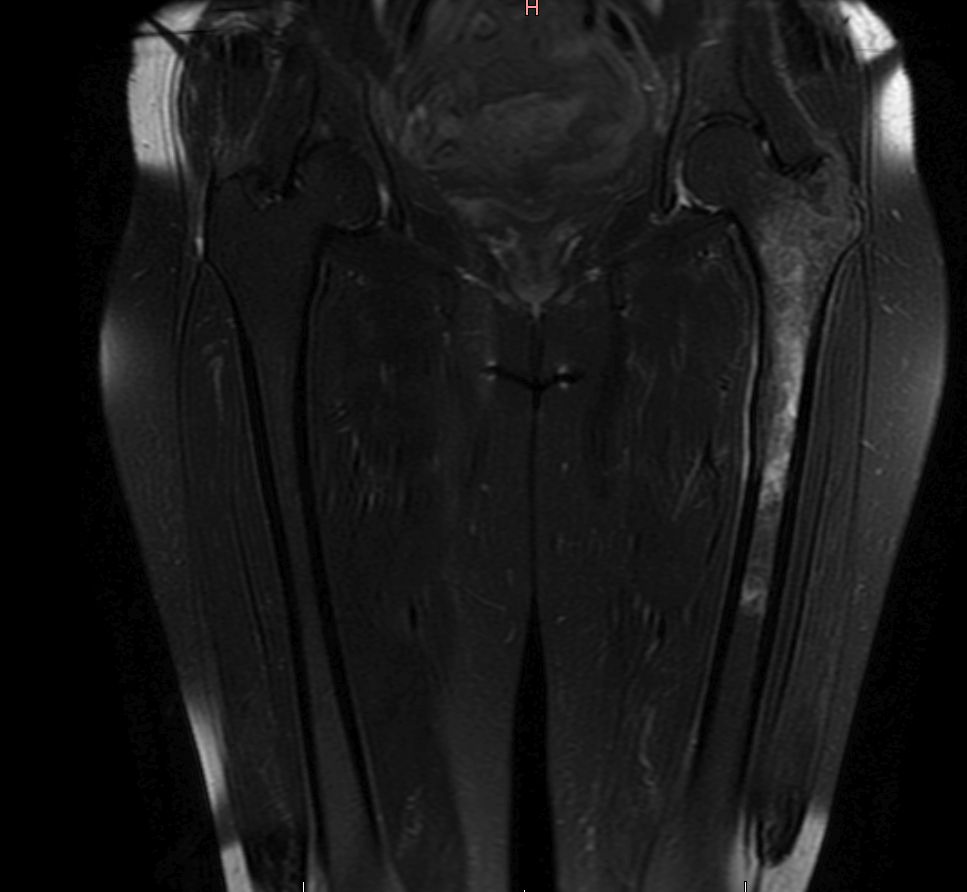

Femur | 58-jährige Frau mit Mammakarzinom links vor 14 Jahren und Mammakarzinom rechts vor 2 Jahren. Seit 4 Monaten Schmerzen im linken Oberschenkel. Jetzt Lungenmetastasen, osteoplastische Metastasen im LWk1 bis LWK4 sowie eine Osteolyse im linken Femur. | ||||||||||

MRT T1 KM Fett-saturiert![]() |

MRT T1 KM Fett-saturiert![]() | ||||||||||